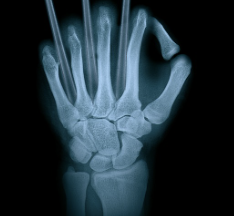

어깨통증을 진단하는 데 가장 중요한 검사는? X-Ray검사!

어깨 통증을 진단하는 데 가장 중요한 검사는 X-ray 검사입니다.

X-ray 검사는 어깨 질환을 진단하는 가장 기본적인 검사 방법으로, 통증의 원인과 양상을 파악하는 데 도움이 됩니다.

하지만 X-ray 검사만으로는 모든 어깨 질환을 정확히 진단하기 어려울 수 있기 때문에 다음과 같은 추가 검사들이 필요할 수 있습니다.